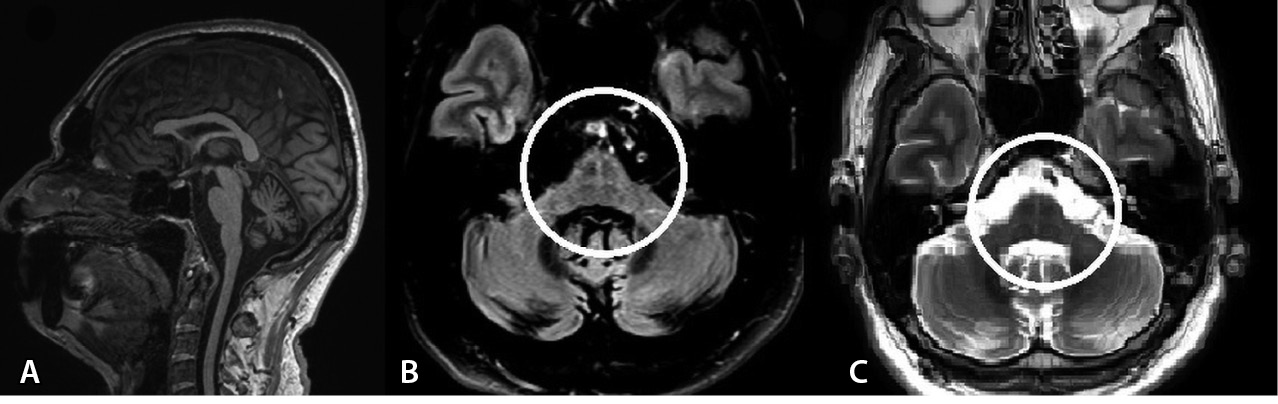

Проведены следующие дополнительные методы исследования. При УЗИ остаточной мочи ее объем составил 105 мл. На магнитно-резонансной томограмме (МРТ) головного мозга – признаки атрофии ствола мозга в режиме Т1, в режиме T2-FLAIR – симптом «креста» (рис. 1).

Рис. 1. Магнитно-резонансная томография головного мозга пациента В. А – Т1-взвешенное изображение, сагиттальный срез: признаки атрофии варолиева моста в виде уплощения его основания, а также расширение борозд мозжечка. Б, В – Т2-FLAIR, Т2-взвешенное изображение, аксиальные срезы: симптом «креста», или “hot cross bun”: гиперинтенсивность волокон мосто-мозжечковых путей и ядер шва (отмечено кругом)